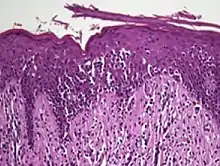

Interface dermatitis with lichenoid inflammation

| Main conditions[2] | Characteristics | Micrograph | Photograph |

|---|---|---|---|

| Generally/Not otherwise specified | Typical findings:[2]

|

||

| Lichen planus | Irregular epidermal hyperplasia with a jagged “sawtooth” appearance, compact hyperkeratosis or orthokeratosis, foci of wedge-shaped hypergranulosis, basilar vacuolar degeneration, slight spongiosis in the spinous layer, and squamatization. The dermal papillae between the elongated rete ridges are frequently dome shaped. Necrotic keratinocytes can be observed in the basal layer of the epidermis and at the dermal-epidermal junction. Eosinophilic remnants of anucleate apoptotic basal cells may also be found in the dermis and are referred to as “colloid or civatte bodies”. Whickham striae are usually seen in the areas of hypergranulosis. Vacuolar degeneration at the basal layer may be noted leading to focal subepidermal clefts (Max Joseph spaces). Squamatization occurs as a result of maturation and flattening of cells in the basal layer. It happens in areas of marked hypergranulosis with prominence of the sawtooth pattern of rete ridges. Wedge-shaped hypergranulosis can occur in the eccrine ducts (acrosyringia) or hair follicles (acrotrichia). In the hypertrophic subtype, the associated hyperkeratosis, parakeratosis, hypergranulosis, papillomatosis, acanthosis, and hyperplasia markedly increased with thicker collagen bundles forming in the dermis. Moreover, the rete ridges are more elongated and rounded as opposed to the typical sawtooth pattern. In atrophic LP, loss of the rete ridges and dermal fibrosis is prominent. In vesiculobullous LP, the disease progression is quicker. Hence, some of the distinctive features such as hyperkeratosis, hypergranulosis, or dense lymphocytic dermal-epidermal infiltrate may not be present. LP lesion may resolve with residual hyperpigmentation caused by a persistent increase in the number of melanophages in the papillary dermis.[9] |  |  |